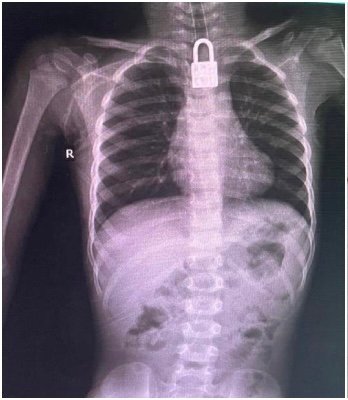

اسپتال ذرائع کے مطابق بچے کے گلے میں تالا پھنس جانے کے باعث سانس کی نالی شدید متاثر ہو چکی تھی اور کسی بھی لمحے جان جانے کا خدشہ تھا۔ طبی معائنے اور ایکسرے رپورٹس کے بعد فوری طور پر ایمرجنسی آپریشن کا فیصلہ کیا گیا، جو کامیابی سے مکمل کر لیا گیا۔

اس حوالے سے چلڈرن اسپتال کے شعبہ کی سربراہ ڈاکٹر نگینہ شہزادی نے بتایا کہ بچے کو سانس رکنے کی شکایت پر لایا گیا تھا، جبکہ تالا گلے میں پھنسنے کے باعث اس کی زندگی کو شدید خطرات لاحق تھے۔ انہوں نے بتایا کہ ماہر ڈاکٹروں کی ٹیم نے نہایت احتیاط اور پیشہ ورانہ مہارت کے ساتھ آپریشن انجام دیا، جس کے نتیجے میں تالا بحفاظت نکال لیا گیا۔

ڈاکٹر نگینہ شہزادی کے مطابق اگر بچے کو بروقت طبی امداد نہ ملتی تو معاملہ جان لیوا ثابت ہو سکتا تھا۔ کامیاب آپریشن کے بعد بچے کی حالت اب خطرے سے باہر بتائی جا رہی ہے اور وہ ڈاکٹروں کی زیر نگرانی تیزی سے صحتیاب ہو رہا ہے۔